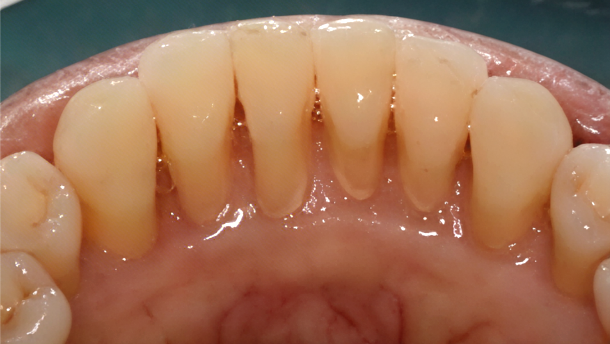

洗牙前VS洗牙后

(徐静医生病例)

洗牙,是口腔护理的基础!许多人不知道,洗牙洗的不仅是“脏东西”,更是牙结石、软垢、菌斑这些导致牙齿发黄、牙龈发炎的“元凶”!通过专业洗牙(龈上洁治),确实能有效去除大部分外源性着色和致病因素,恢复“红(牙龈)白(牙齿)美学”,让口腔呈现自己真实的美貌和健康。

定期洗牙可以预防牙周炎的发生,或者让已经形成的牙周炎症得到有效控制。